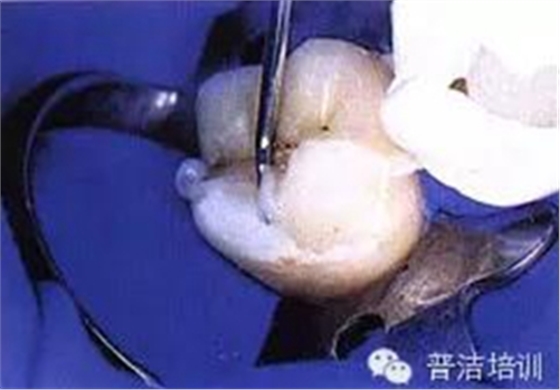

二、去除齲壞的組織,可以使用送風(fēng)公司生產(chǎn)的齲齒檢測液來判斷齲壞的組織是否去除干凈

三、牙體預(yù)備完成,,邊緣預(yù)備短斜面(45度),短斜面這點(diǎn)很多書上沒具體說,想想還是有必要的,但在金屬嵌體和瓷嵌體就沒必要了。其實(shí)預(yù)備這一步驟沒什么高深莫測的,多加訓(xùn)練,端正態(tài)度就可以。